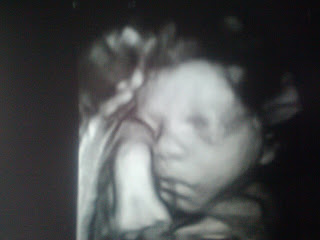

Some pictures from this week's ultrasound:

I just love the smirk in this one! :)

He's got my nose

Profile